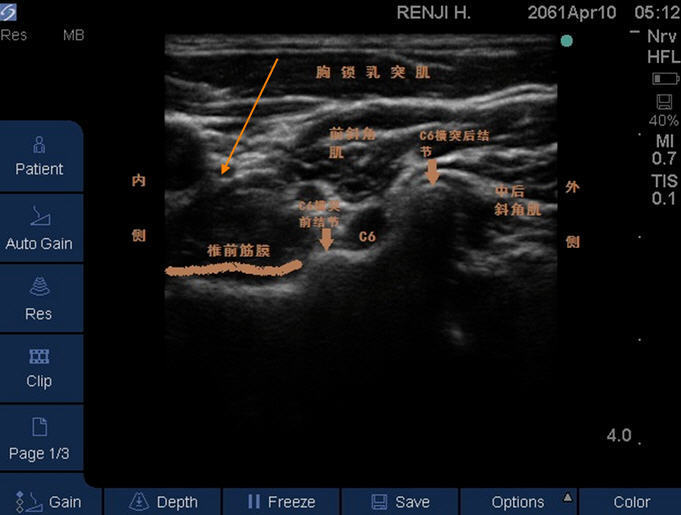

颈源性头痛是一种牵涉痛,是由颈椎和/或颈部软组织的器质性或功能性病损所引起的以慢性、单侧头痛为主要临床表现的综合征。头痛发作的同时伴有上颈部疼痛、僵硬或活动时上颈部疼痛、压痛、颈部活动受限,病因多为椎间盘退行性变引起的神经压迫和伴随的局部无菌性炎症。星状神经节阻滞是指将局部麻醉药注射到星状神经节的表面,使其被药液浸润,从而阻断所支配区域的交感活动的方法。解剖颈交感神经链纤维起源T1-T6脊髓,沿颈部上升在颈长肌和头长肌之前。它们位于颈动脉的后内侧椎前筋膜。这些细胞聚集在一起形成上、中、下颈交感神经神经节。颈上交感神经节是交感神经链的最上神经节,以及其与椎骨水平的关系不同。Mistuoka等人,它处于C2、C3水平,而Erdinc等认为它处于C4水平。颈上交感神经节有节后瞳孔扩张肌的纤维颈外动脉、心丛、咽丛、CNIX、X和灰交通支C1-C4脊神经。MitsuokaK,KikutaniT,SatoI.Morphologicalrelationshipbetweenthesuperiorcervicalganglionand cervicalnervesinJapanesecadaverdonors.BrainBehav2017;7:e00619. CivelekE,KarasuA,CanseverT,etal.Surgicalanatomyofthecervicalsympathetictrunkduringanterolateralapproachtocervicalspine.EurSpineJ2008;17:991-995.颈中交感神经节的位置是可变的通常在C6水平,但可以高达C5和低至C7,有时可能不存在。它的节后纤维有助于C5、C6灰支通讯以及心脏丛。颈下交感神经节位于C7层与第一胸神经节融合形成星状神经节神经节(图3)。它发出灰色的信号至第七和第八颈脊神经及其节后纤维有助于心丛。适应症复杂区域疼痛综合征I型和II型上肢和交感神经介导的疼痛头部和面部疼痛卒中后丘脑介导的疼痛。癫痫病例报告WangS,ZhuY.Acasereportofstellateganglionblockinthetreatmentofepilepticpain.Medicine(Baltimore)2017;96:e6044.LiaoC,YangM,LiuP,ZhongW,ZhangW.Thalamicpainalleviatedbystellateganglionblock:Acasereport.Medicine(Baltimore)2017;96:e6058.机制星状神经节是支配头、颈、肩及上肢的主要交感神经节,星状神经节阻滞能在不降低脑灌注、不改变脑的自身调节功能前提下,降低支配区域的血管紧张度,改善其支配区域的血流,从而改善头颈部的血供。 可很好地调节头部植物神经功能,减少其紊乱。阻断各种病灶部位的不良刺激,使头部面部血管扩张,痉挛缓解,灌流量增加;患区血液循环改善可使致痛物质的释放量减少,使疼痛减轻;同时局部痉挛的肌肉得以缓解,使疼痛进一步减轻。头面部由三叉神经及第2、3颈神经所支配,绝大多数头痛可能与颈椎的病理改变有关。而且三叉神经传出支与上部颈神经传出支在解剖上汇合。同时还存在着位于副神经、上颈部颈神经根和三叉神经下行束之间的内部联系,这就是斜方肌和胸锁乳突肌疼痛向头面部传递的基础。星状神经节阻滞还能抑制交感神经兴奋性,交感神经阻滞后PGs的合成与释放减少由此降低其他炎症介质(如IL-6,IL-8和TNF-a)的反应性和表达水平及P物质的释放,减轻疼痛应激。向勇,刘菊英,朱涛,等.星状神经节阻滞对脑源性神经营养因子和白介素一8的影响[J].中华物理医学与康复杂志,2005,27:205-208。操作技术患者仰卧颈部略微伸展,头部转向相反侧。线性传感器已定位在环状软骨层(C6椎体层)的SCM后面。识别Chassaignac的C6横突的(前)结节,其大于其后结节。它是一个有助于鉴别的超声特征来自C7,其横突缺少前结节。颈下/星状神经节位于后颈长肌的前方包裹椎前筋膜。星状神经节阻滞,面内入路,22-25G从后外侧到前内侧,指向脊椎前筋膜颈动脉和C6前结节尖端,颈长肌前(图)。SCM:胸锁乳突肌;PVF:椎前筋膜;LCap头长肌、LColi:颈长肌;CA:颈动脉;AT:C6前部结节;PT:C6后结节;C6NR:C6神经根;箭头指示穿刺针轨迹。在C4水平,颈上神经节在头长肌的前面椎前筋膜下的肌肉。SCM:胸锁乳突肌;IVF:中层筋膜;PVF:椎前筋膜;LCap:头长肌;LColi:颈长肌CA:颈动脉;AT:C4前结节;PT:C4后结节;箭头指示穿刺针轨迹。椎前筋膜平面下注射10mL局部麻醉剂。成功闭塞的迹象有以下一种或多种症状和体征:患者患同侧霍纳综合征(上睑下垂、瞳孔缩小和无汗)、鼻塞、,面部潮红或上肢温度升高。症状将在大约10分钟后出现分钟,持续数小时,具体取决于使用局部麻醉剂。治疗头部和面部时疼痛和创伤后应激障碍,有些人更喜欢阻断C4和C6水平的颈神经节每个部位注射5mL。尽管一项研究表明,通常使用总共10mL的注射剂显示在C6注射了5mL局麻药水平足以从C4分布到T3。这个最常用的注射药物是局部麻醉剂。可乐定、氯胺酮和丁丙诺啡(神经节局部阿片镇痛也有研究,但证据有限。FeiglGC,RosmarinW,StelzlA,WeningerB,LikarR.Comparisonofdifferentinjectatevolumesforstellateganglionblock:Ananatomicandradiologicstudy.RegAnesthPainMed2007;32:203-208.NascimentoMS,KlamtJG,PradoWA.IntravenousregionalblockissimilartosympatheticganglionblockforpainmanagementinpatientswithcomplexregionalpainsyndrometypeI.BrazJMedBiolRes2010;43:1239-1244.GoebelA,LawsonA,AllenS,GlynnC.Buprenorphineinjectiontothestellateganglioninthetreatmentofupperbodychronicpainsyndromes.EurJPain2008;12:266-274.KulkarniKR,KadamAI,NamaziIJ.Efficacyofstellateganglionblockwithanadjuvantketamineforperipheralvasculardiseaseoftheupperlimbs.IndianJAnaesth2010;54:546-55